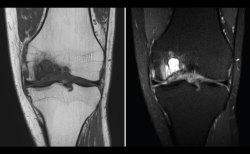

4.3. Osteocondritis

En la osteocondritis se aprecia una lesión subcondral caracterizada por resorción ósea, colapso y la formación de un secuestro.

El estudio por RM es una herramienta valiosa para diagnosticar e identificar las lesiones del cartílago. Conocer el aspecto del cartílago y saber cuánto y cuándo se lesiona, basándose en las clasificaciones actuales, permiten al radiólogo proporcionar la máxima información al clínico(20).

Figura 53. Corte de secuencia sagital (A) y axial (B) T2 Fat-Sat de RM de rodilla: lesiones osteocondrales en el fémur y la rótula.

Numerosos estudios demuestran la utilidad de la RM para definir la estabilidad o inestabilidad de la lesión en la osteocondritis, destacando su carácter no invasivo y la capacidad de valorar la progresión y la respuesta al tratamiento(21)(Figuras 53 y 54).